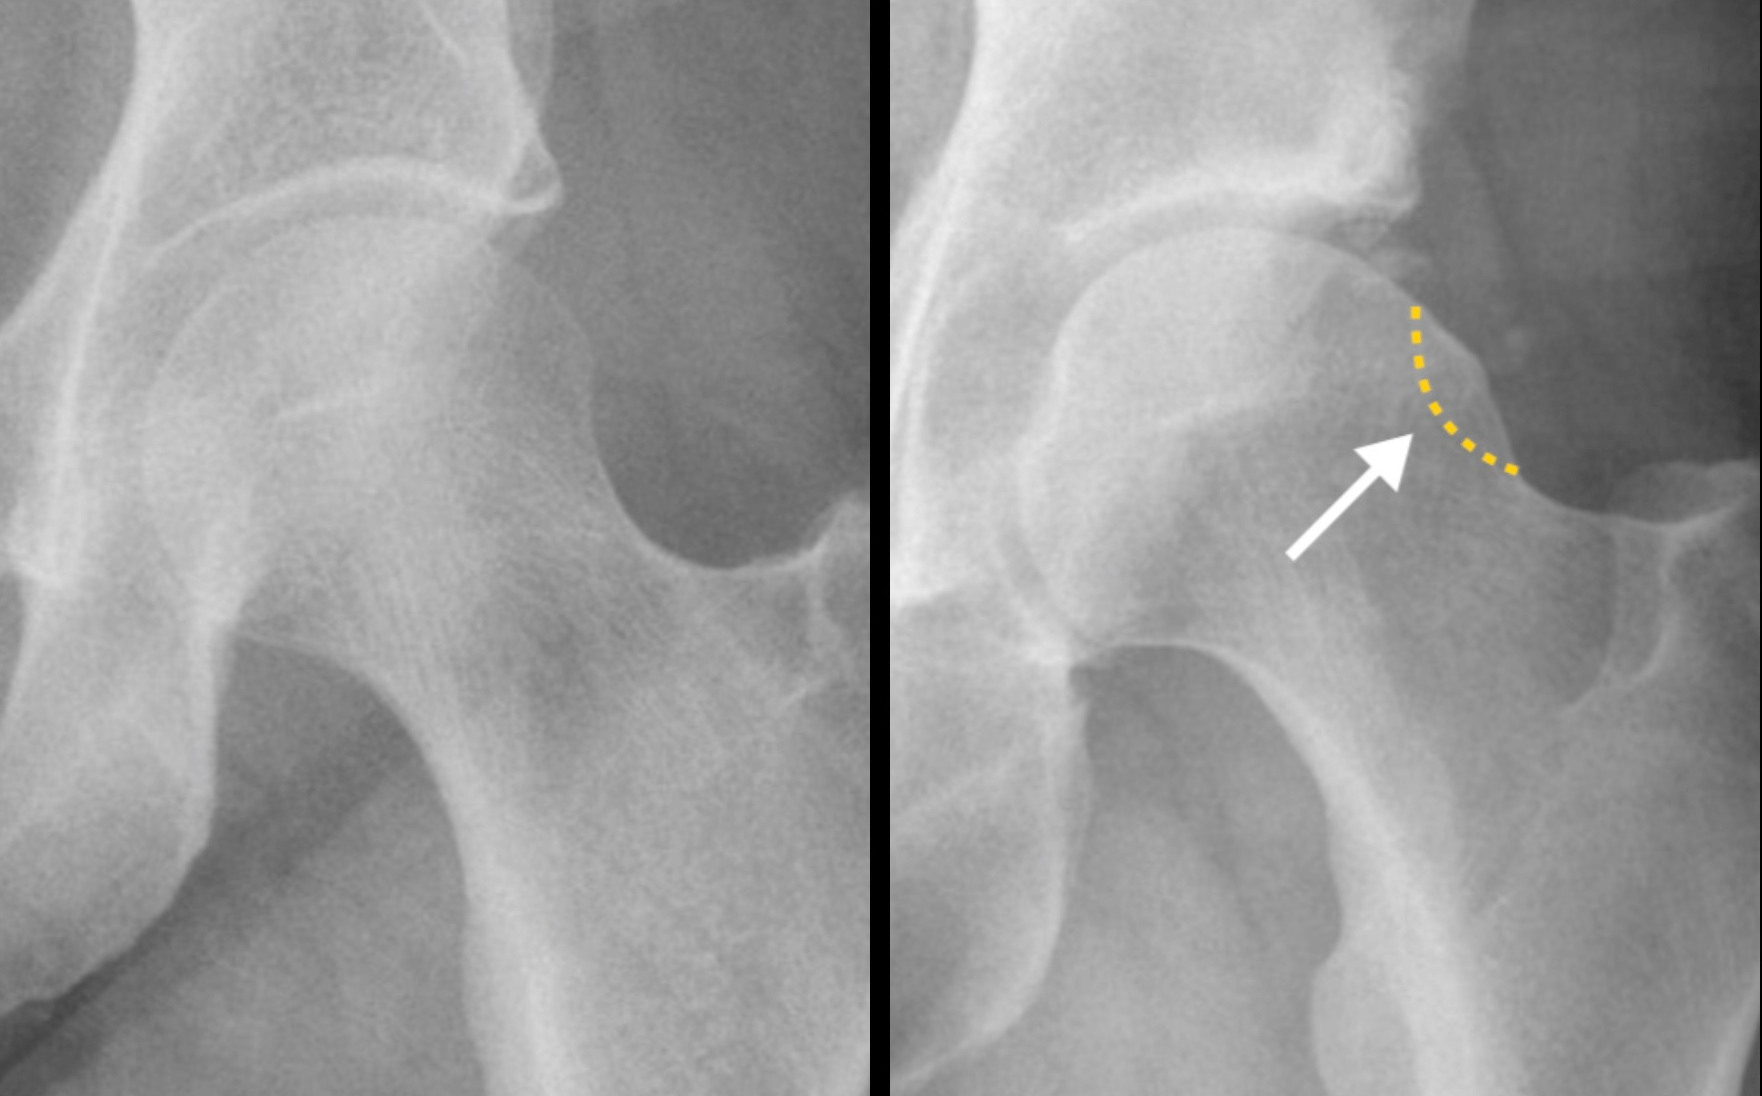

Basic modalities of cam type deformity. On the anteriorposterior Cam Type Deformity Treatment This involves reducing or avoiding activities that cause or aggravate symptoms. What are the treatments for femoroacetabular impingement (fai)? Fai treatment varies according to the person and the severity of the. If the head is not shaped normally, the abnormal part of the. Treatment may be nonoperative or operative depending on the chronicity of symptoms, patient age, patient activity demands,. Cam Type Deformity Treatment.